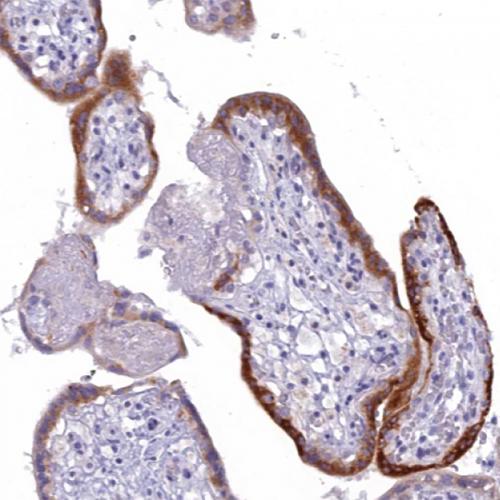

我國胃癌發(fā)病率居惡性腫瘤第2位,新發(fā)病例68萬例,死亡49萬例。研究表明:HP感染者均會引起慢性活動性胃炎,在胃黏膜萎縮和腸化生的發(fā)生和發(fā)展中也起重要作用[1],HP感染和胃癌的發(fā)生密切相關(guān),根除HP是預(yù)防胃癌的有效措施。IHC染色特異性強(qiáng)、靈敏度高、陽性準(zhǔn)確性高、易于判讀,便于各級醫(yī)院病理科開展業(yè)務(wù),特別適合胃鏡活檢標(biāo)本量較大的情況,值得推廣[2-3]